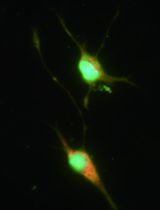

We recently published the isolation and extensive characterisation of a population of non-adherent endothelial forming cells (naEFCs) (Appleby et al., 2012) (Figure 1). These cells expressed the progenitor cell markers (CD133, CD34, CD117, CD90 and CD38) together with mature endothelial cell markers (VEGFR2, CD144 and CD31). These cells also expressed low levels of CD45 but did not express the lymphoid markers (CD3, CD4, CD8) or myeloid markers (CD11b and CD14) which distinguishes them from ‘early’ EPCs, the ‘late outgrowth EPC’ [more recently known as endothelial colony forming cells (ECFCs)] as well as mature endothelial cells (ECs). Figure 2A exemplifies the surface expression profile of the naEFCs. Functional studies demonstrated that these naEFCs (i) bound Ulex europaeus lectin (Figure 2A), (ii) demonstrated acetylated-low density lipoprotein uptake, (iii) increased vascular cell adhesion molecule (VCAM-1) surface expression in response to tumor necrosis factor and (iv) in co-culture with mature ECs increased the number of tubes, tubule branching and loops in a 3-dimensional in vitro matrix. More importantly, naEFCs placed in vivo generated new lumen containing vasculature lined by CD144 expressing human ECs and have contributed to various advances in scientific knowledge (Appleby et al., 2012; Barrett et al., 2011; Moldenhauer et al., 2015; Parham et al., 2015). Here, we describe the isolation and enrichment of a non-adherent CD133+ endothelial forming population of cells from human cord blood.

Figure 1. Enrichment of human naEFCs. A. Umbilical cord blood derived CD133+ enriched cells (naEFCs) at 4 days of culture and human umbilical vein endothelial cells (ECs) were compared for cell size by light microscopy. Scale bar=200 µm B. The cells were assessed for heterogeneity of enrichment process (0-10 days) via forward scatter and side scatter profiling using flow cytometric analysis and compared to mature ECs.